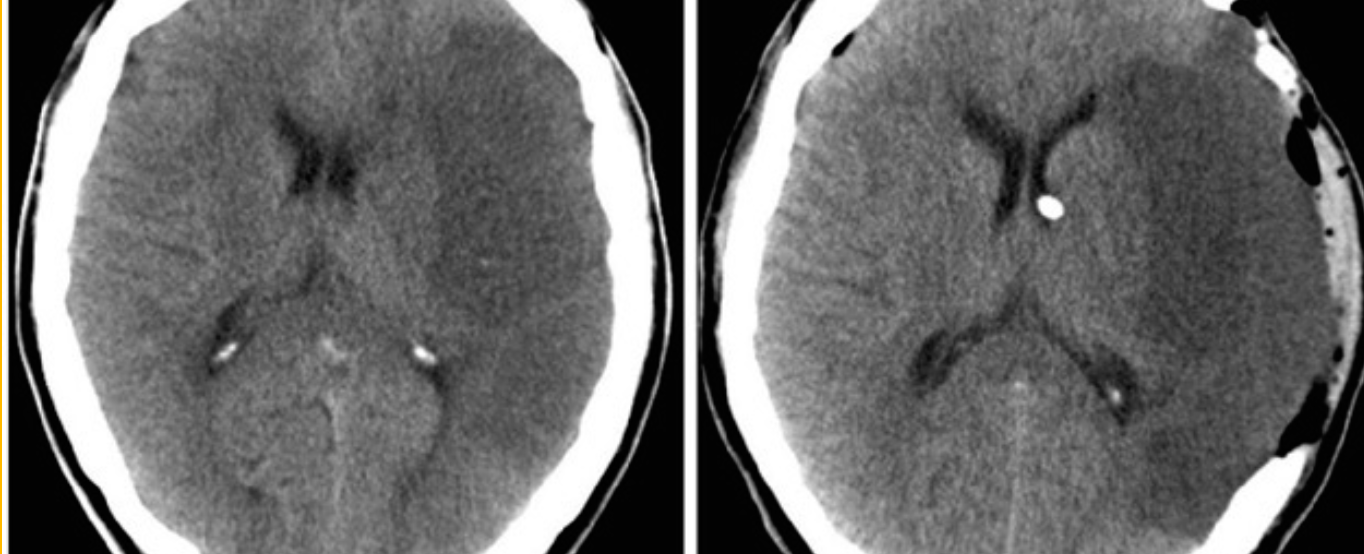

Case 7 Z

Describe 2 abnormal findings of the CT?

- a. ---pressure of lf lobe---

- c. ---Hypodense in left lobe---

Name vascular territory involved? - ---medial cerebral artery---